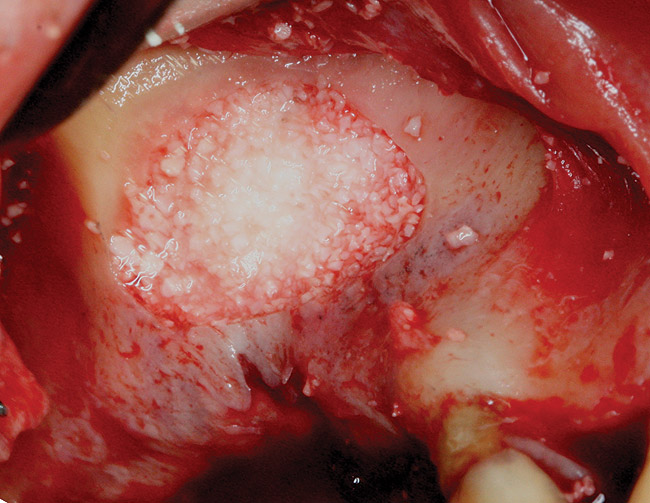

Fig 4. Space is created between the Schneiderian membrane and the sinus walls filled with particulate xenograft.

Figure 4

The technique described below is based on a deep buccal full-thickness flap with vertical release in the canine area, followed by creation of a “window” at the lateral wall of the sinus (Figure 2). The bony window is either removed or rotated medially with the sinus membrane and pushed inward. The Schneiderian membrane is then separated from the bone anteriorly, posteriorly, and medially until clinically sufficient space is established (Figure 3). The created space, which occupies the lower third of the sinus, is filled with a bone graft (Figure 4), and the lateral access window is covered with a collagen membrane (Figure 5).